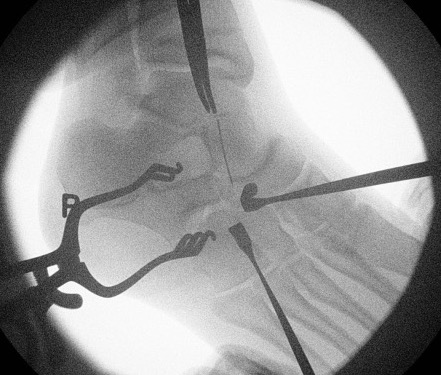

Resection

- resect 1cm of bone with osteotomes

- check with on table oblique intra-operative image

- interpose fat / EDB / bone wax into defect